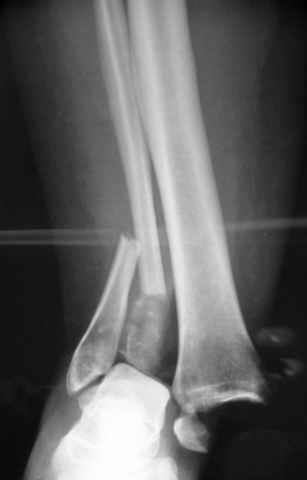

Pilon fracture:

ET> ЕЧ При подобных переломах фиксация малоберцовой кости обеспечивает

ET> низведение латерального тибиального фрагмента - появляется ориентир для

-Появляется ориентир и остов, на чем можно строить восстановление, почему сперва малоберцовую, впервые обьяснили и описали (Pylon type and Ankle fractures) в середине 50х Rienau и Gay.

Восстановливая длину и ротацию малоберцовой кости, затем относительно легче произвести реставрацию остальных элементов перелома дистального эпиметафиза болшеберцовой кости.

где исследования на трупах показали, что малоберцовая кость участвует в стабильности голеностопного сустава, поддерживая наклон тарана (talar tilt) за счет связок. После ознакомления работой Ramsey в ортопедию ввели термин "при переломах голеностопного сустава смещенная

таранная кость следует за малоберцовой костью" т.е. связка не рвется, а тянет таран за собой, поэтому восстановление малоберцовой кости в

первую очередь, затем остальных элементов - стал классическим при лечении данной патолгии. Латеральная колонна (столб), дистальный

конец малоберцевой кости, к нему прикрепляется латеральный суставной фрагмент дистального эпиметафиза большеберцовой кости (как на снимке)

и таранная кость, которые при репозиции малоберцовой кости репонируются автоматически.